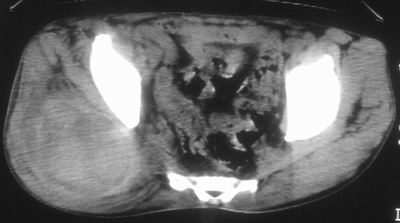

标题: CT16837:M63Y,右臀部巨大软组织包块 [打印本页]

标题: CT16837:M63Y,右臀部巨大软组织包块

患者,男,63岁,自诉3个月前发现右臀部包块,触及疼痛,治疗后缩小。前天突然增大。无高热病史。

给个骨窗,判断一下肿块是否与髂骨有关,肿块内出血是肯定的,至于是感染形成的脓肿还是起源于肌肉或纤维组织的肉瘤则难以确定,不过从影像上看,包膜完整,且环形增厚,病灶下部见斑片状底密度坏死,个人倾向感染可能性大

肌间隙明显混浊,三个月前治疗有缩小,支持考虑臀大肌下脓肿伴出血,肿瘤如果出现瘤内出血的话瘤外边界应该较清楚,现在表现为一种恶性征像,但骨质无明显异常,且臀小肌边界清楚,不符合恶性表现.